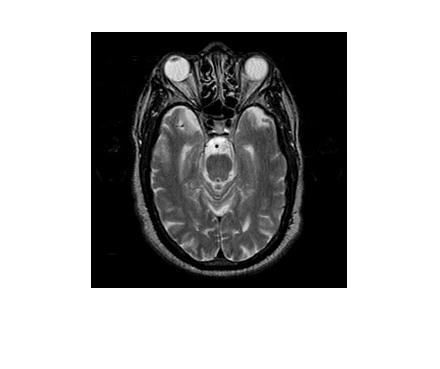

基于拉普拉斯重分解的多模态医学图像融合,核心是通过多尺度、精细化的拉普拉斯重分解拆分图像的低频结构与高频细节,再针对医学图像的临床需求(如结构完整性、病灶凸显性)设计分层融合规则,实现 CT/MRI、PET/CT 等多模态图像的信息互补,为临床诊断与手术规划提供更全面的视觉支撑。该方法突破传统拉普拉斯金字塔 “单一尺度分解” 的局限,通过重分解增强细节分离能力,兼顾融合精度与医学实用性。

多模态医学图像的融合目标是互补不同模态的优势信息:

CT 图像:清晰呈现骨骼、钙化灶等高密度组织,但软组织对比度低;

MRI 图像(T1/T2 加权):精准区分软组织(如肿瘤、水肿),但对骨骼显示模糊;

PET 图像:反映代谢活性(如肿瘤恶性程度),但空间分辨率低、结构模糊。融合需实现 “结构 + 功能 + 细节” 的三维互补,确保医生能同时观察解剖结构与病理特征。